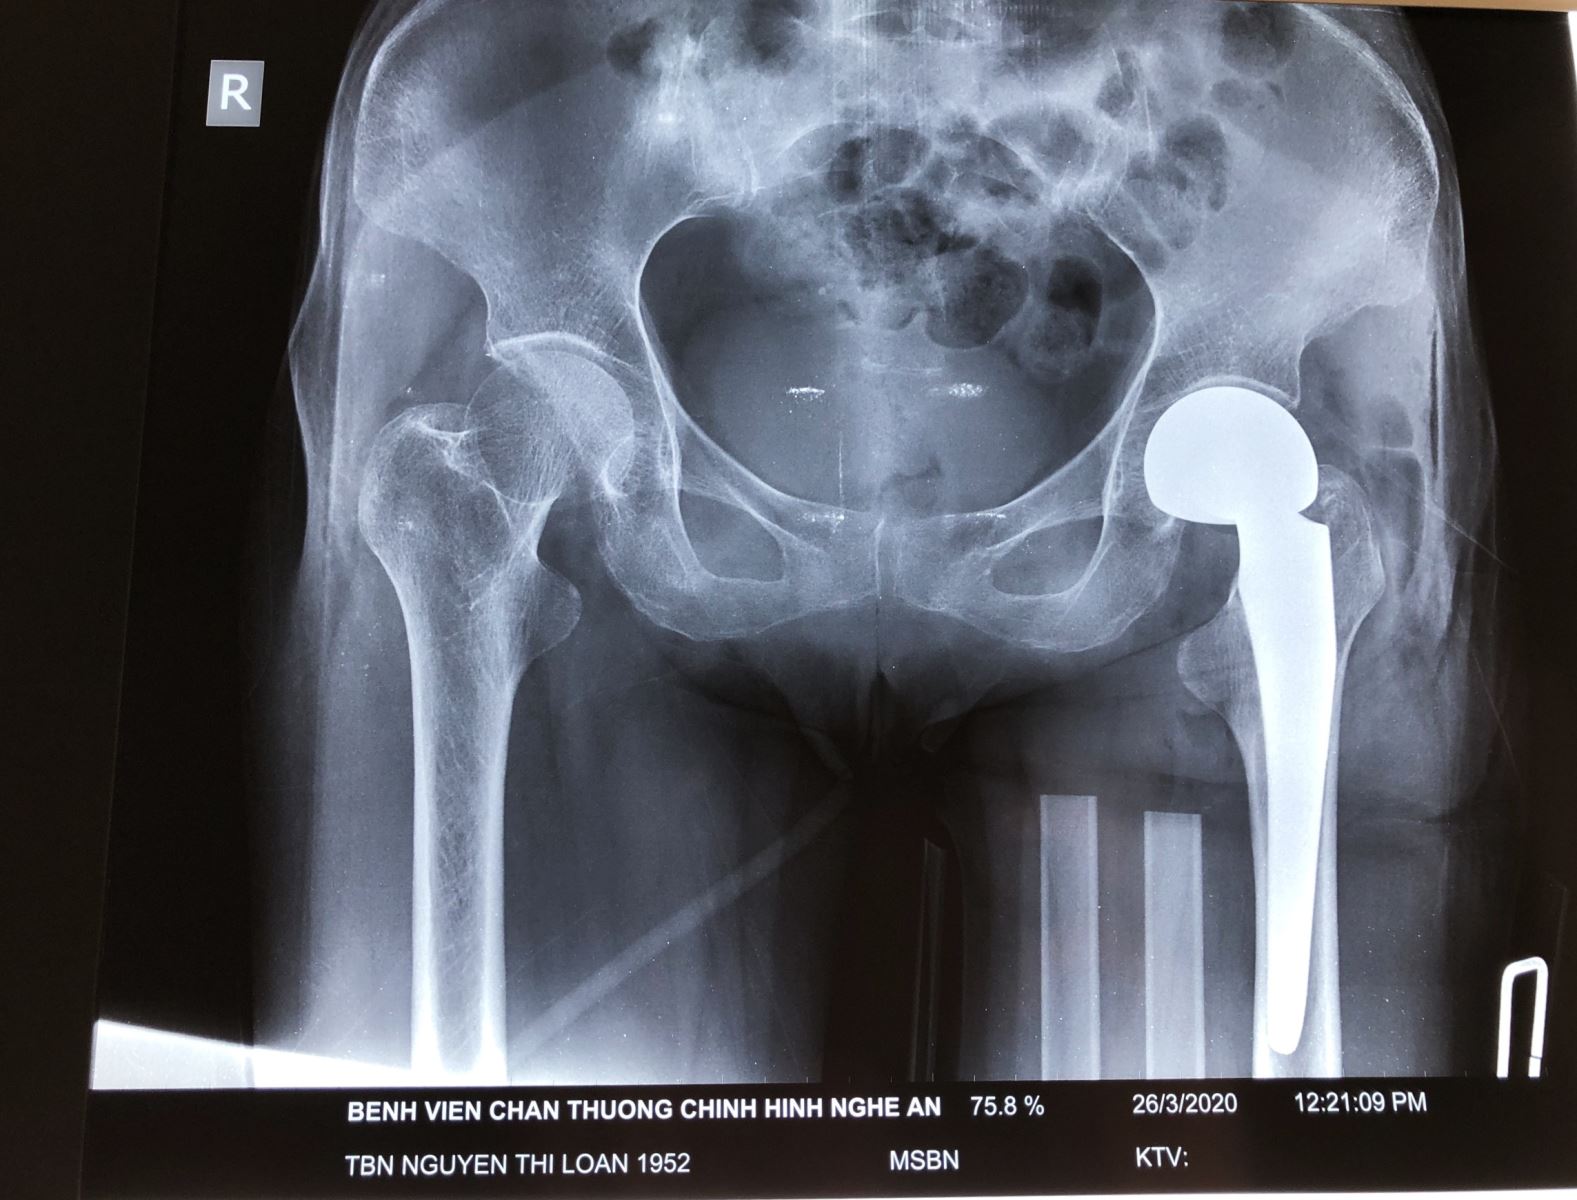

Hình ảnh phim chụp Xquang của bệnh nhân trước và sau phẫu thuật thay khớp háng

Bệnh nhân Nguyễn Thị Loan, 68 tuổi, ở TP.Vinh – Nghệ An có tiền sử parkinson, đã điều trị 6 năm nay. Đợt này bệnh nhân trượt chân ngã gây đau biến dạng, hạn chế vận động đùi háng trái. Vào Bệnh viện Chấn thương Chỉnh hình Nghệ An, bệnh nhân được chẩn đoán gãy cổ xương đùi trái.

Sau khi tiến hành hội chẩn, bệnh nhân được chỉ định phẫu thuật thay khớp háng bán phần. Ca phẫu thuật được tiến hành thành công bởi kíp mổ của ThS, Bác sĩ Nguyễn Hoài Nam – Giám đốc Bệnh viện và các cộng sự.